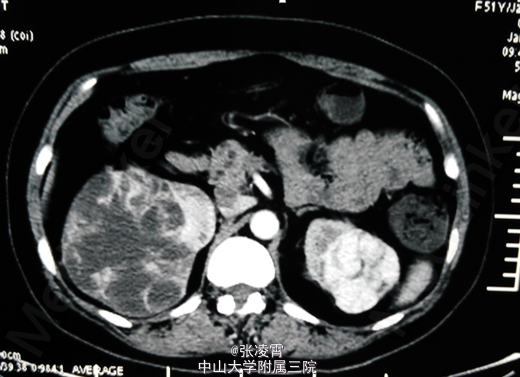

腹部超声:右肾混合性占位性病变(中下极见一个大小约90*65*83mm的混合回声团,边界尚清,内回声不均,可见密集分布的无回声囊,呈蜂窝状);右肾局限性积液;胰腺内异常回声(多个大小不等的无回声囊,大者约12*11mm,边界清);双侧卵巢小囊(27*25mm(右)、25*25mm(左));肝、胆、脾未见明显异常;左肾、膀胱未见明显异常;双侧输尿管未见明显扩张;子宫未见明显异常。腹部增强CT ,胰腺多发囊性病变,右肾巨大占位,考虑肾癌。